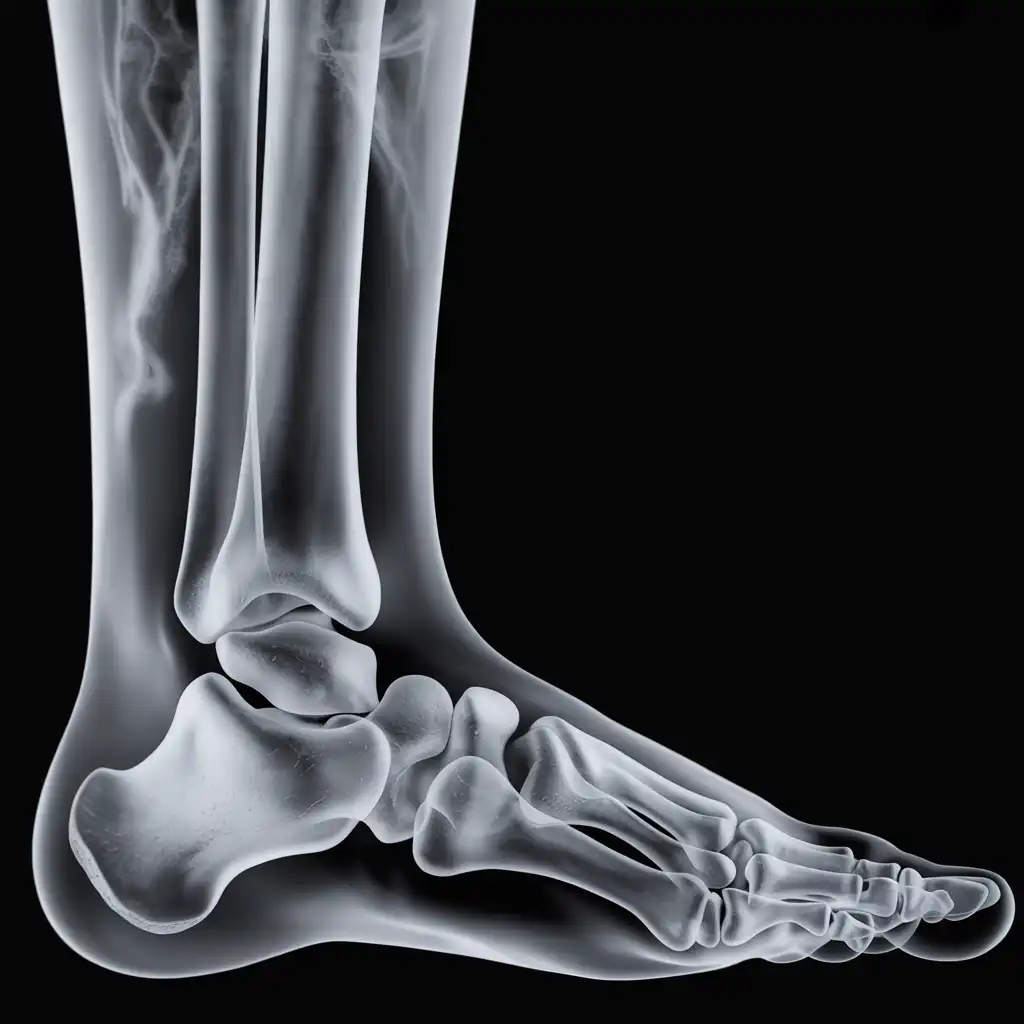

Una radiografia a domicilio è un esame radiologico eseguito da un tecnico specializzato che viene a casa tua con apparecchiature digitali portatili. L’esame si svolge sul posto, senza spostare il paziente e con la stessa qualità di una struttura ospedaliera.